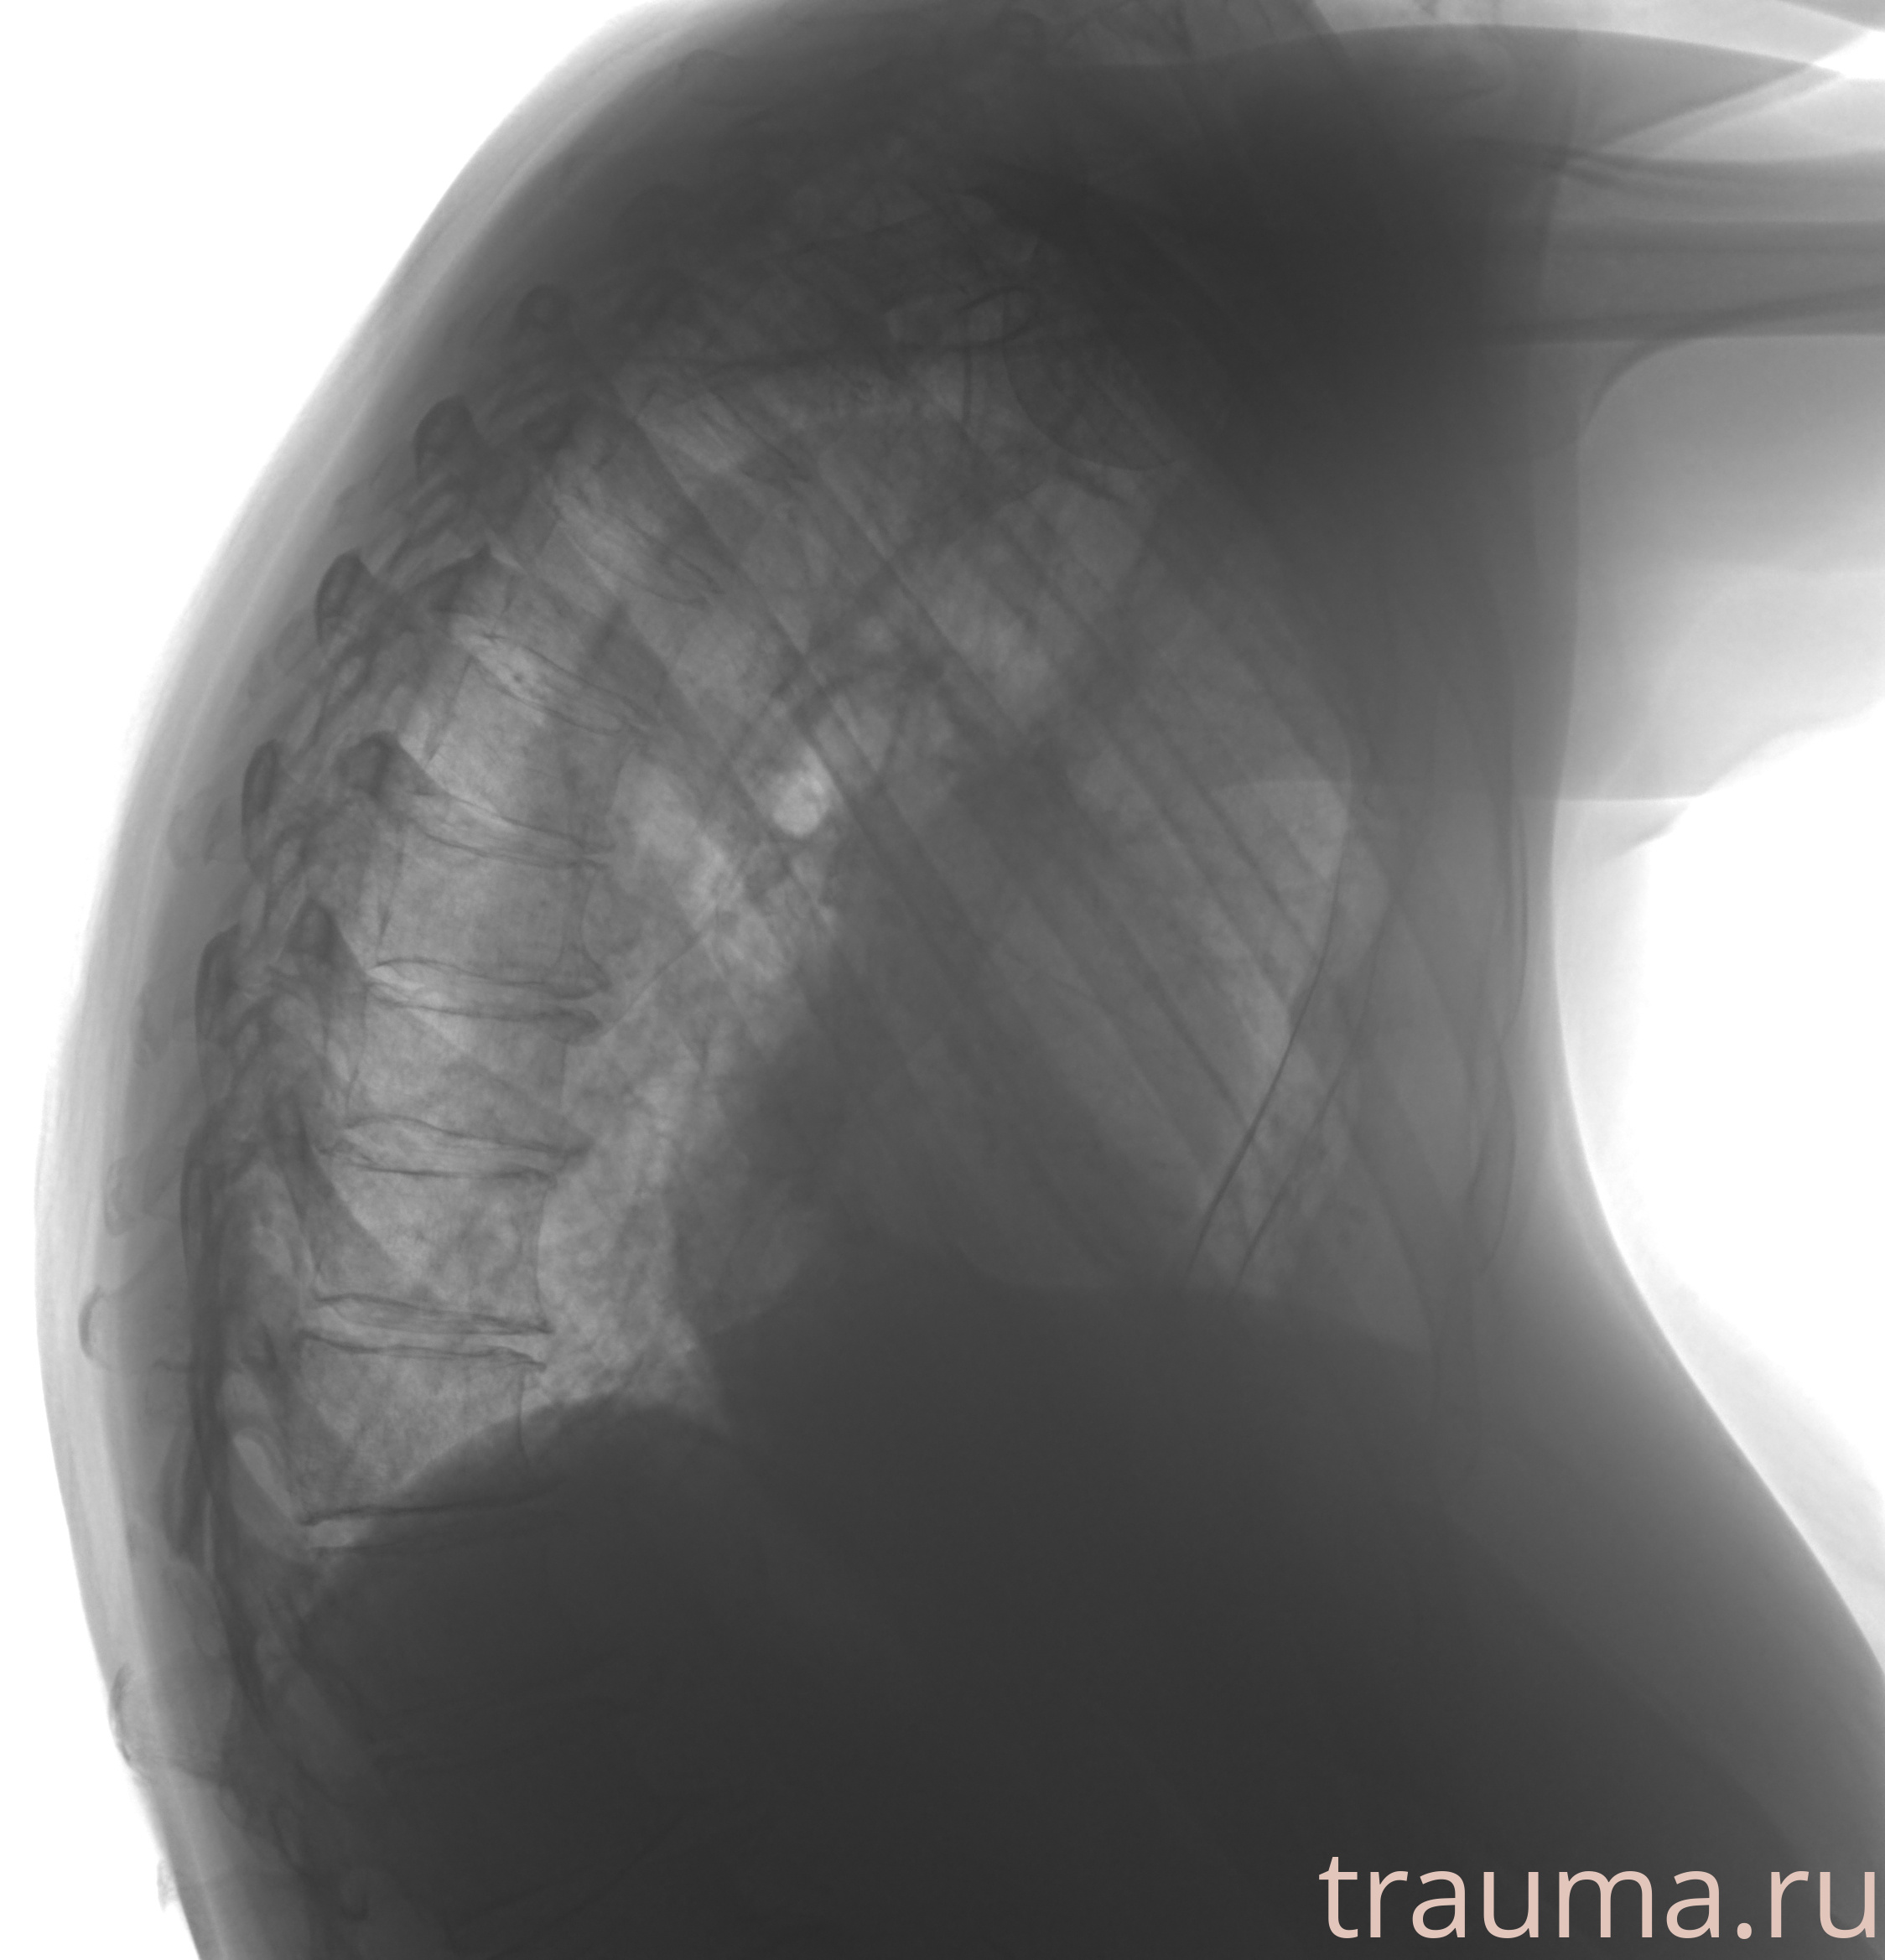

Рентген на дому: по вашему адресу приезжает врач-рентгенолог, травматолог-ортопед с мобильным рентгеновским аппаратом, проводит диагностику травмы или заболевания, делает необходимые рентгенограммы, дает рекомендации по дальнейшему лечению. Получить качественные снимки в домашних условиях возможно благодаря уникальной методике, разработанной МосРентген Центром для института  Склифосовского

при переломе шейки бедра и пневмонии от компании МосРентген Центр - партнера Института имени Склифосовского